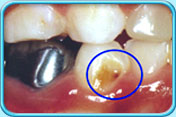

图中所见是蛀坏的牙齿补牙前的外貌。补牙前

图中所见是蛀坏的牙齿以汞合金填补后的外貌。补牙后